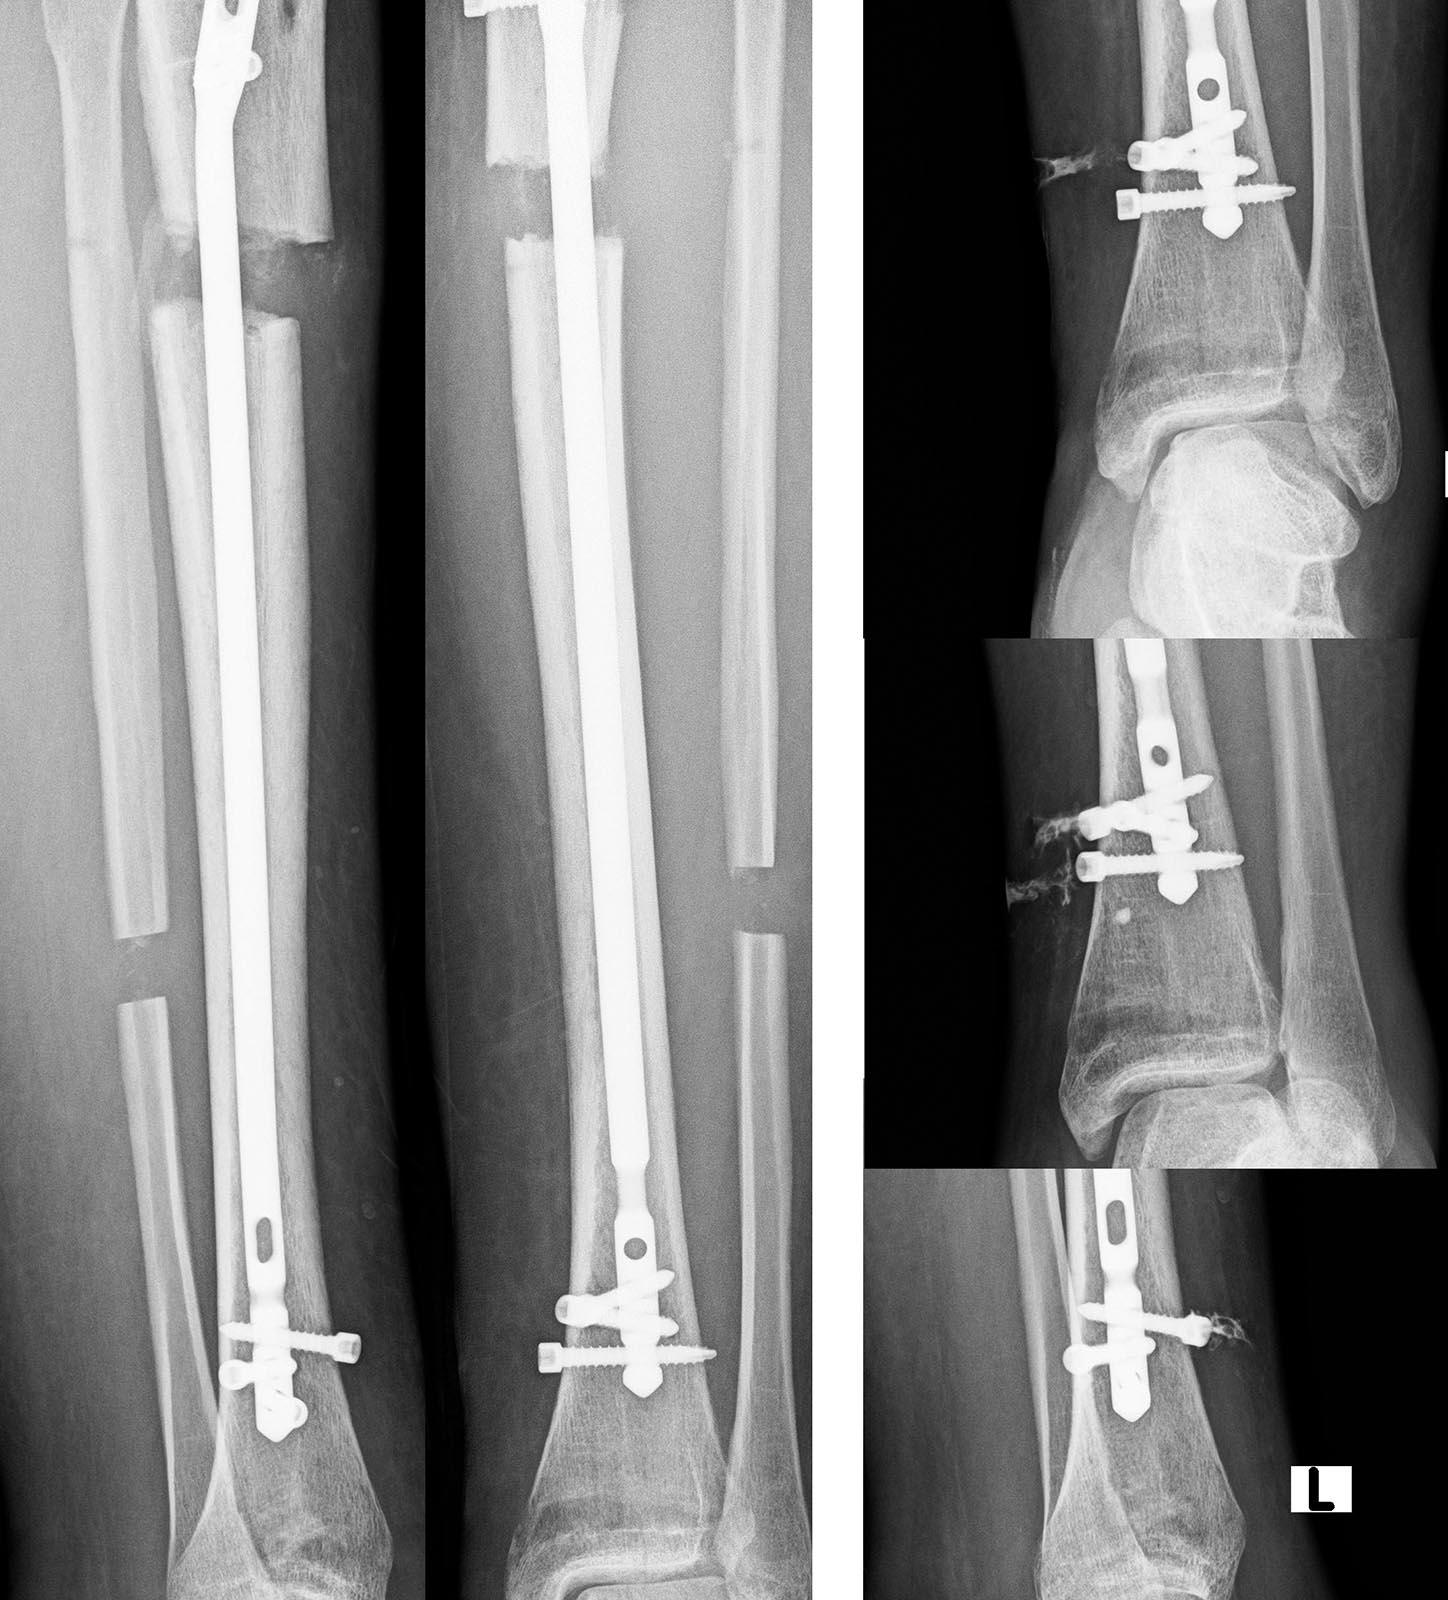

Спасибо всем, кто принял участие в обсуждении. Штифт удален, спейсер ванкомицин 2г + амикацин 1,5 г. Через 2-3 недели планируется удалить спейсер и наложить спице-стержневой аппарат Илизарова. Рентгенограммы прилагаются.